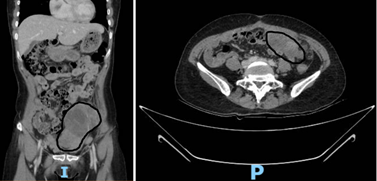

546368638-1370365445092089-42700856092799054-n.jpg

Hình 2. Hình ảnh vị trí to nhất của khối u trên CTscan bụng theo các mặt cắt đứng dọc và ngang sau khi hóa trị - Ảnh BVCC

Sau khi có chẩn đoán xác định, bệnh nhân được chỉ định hóa trị 6 chu kỳ. Nhờ đáp ứng tốt, khối u thu nhỏ đáng kể. Đến lần phẫu thuật thứ hai (second look surgery), ê-kíp ghi nhận: nhiều khối u thành bụng, u vùng chậu và u mạc treo đại tràng (T) kích thước từ 4–10cm, cùng khối u buồng trứng (P) 5cm.

Các khối u chắc, giới hạn rõ, có thể cắt bỏ được. Các bác sĩ đã tiến hành cắt bỏ khối u và các tổn thương liên quan, đạt được tiêu chuẩn triệt để về ung thư học.